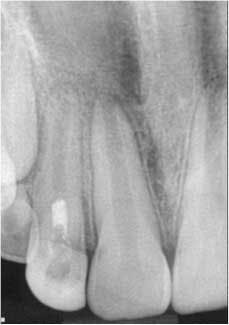

At the second visit, the tooth was anesthetized with an anesthetic that had no vasoconstrictors (to increase the likelihood of getting a blood clot in the tooth, Petrino et al., 2010), isolated, and accessed. The canals were irrigated with 20 ml of 5.25% NaOCl. After irrigation, the canal system was dried and a small, stainless steel hand file was used to lacerate the periradicular tissue to induce bleeding into the canal system. Once there was evidence of blood flow back into the canal, Collaplug (Zimmer Dental, Carlsbad, Calif.) was placed into the canal system to help create a barrier at the coronal portion of the canal. After formation of the blood clot, white MTA was condensed on top of the Collaplug to seal the canal system. The tooth was temporized, and the patient was instructed to return to his general dentist for restoration of the access (Fig. 2).Fig. 2: Tooth No. 7 after second visit showing placement of the MTA barrier.The patient was placed on recall and returned approximately eight months following treatment. The patient and parent reported that the tooth was not restored, but had been asymptomatic. Clinically, the tooth was asymptomatic, and radiographs showed signs of resolution of the apical radiolucency, increased thickness of the root walls, and apical closure. The patient was encouraged to have the access restoration restored. (Fig. 3) The patient returned at 15 months for his next recall examination, and the tooth had a permanent restoration. Clinically, the tooth was asymptomatic, and radiographs showed evidence of apical bone healing, increased thickness of the root walls, and apical closure. (Fig. 4)

Fig. 4: 15-month recall. Note the continued apical development and intact and uniform PDL and LD. Also note the hard-tissue barrier apical to the MTA.